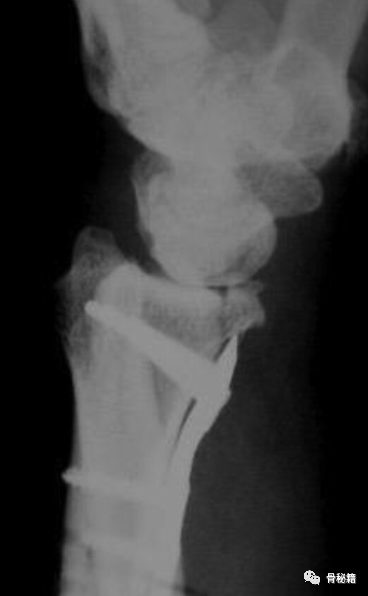

掌侧的一个边缘剪切骨折伴有脱位,采用边缘克氏针固定。

可见骨折固定良好,关节稳定